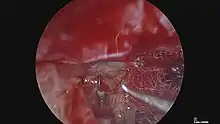

There are various methods to treat otosclerosis. However the method of choice is a procedure known as stapedectomy.[29] Early attempts at hearing restoration via the simple freeing of the stapes from its sclerotic attachments to the oval window were met with temporary improvement in hearing, but the conductive hearing loss would almost always recur. A stapedectomy consists of removing a portion of the sclerotic stapes footplate and replacing it with a middle ear implant that is secured to the incus. This procedure restores continuity of ossicular movement and allows transmission of sound waves from the eardrum to the inner ear. A modern variant of this surgery called a stapedotomy, is performed by drilling a small hole in the stapes footplate with a micro-drill or a laser, and the insertion of a piston-like prothesis. The success rate of either surgery depends greatly on the skill and the familiarity with the procedure of the surgeon.[17] However, comparisons have shown stapedotomy to yield results at least as good as stapedectomy, with fewer complications, and thus stapedotomy is preferred in normal circumstances.[30] Recently, Endoscopic stapedotomy has been gaining popularity since its first description by Professor Tarabichi in 1999.[31] The endsocope provides much better view of the stapes footplate without removal of bone to access that structure.[32]